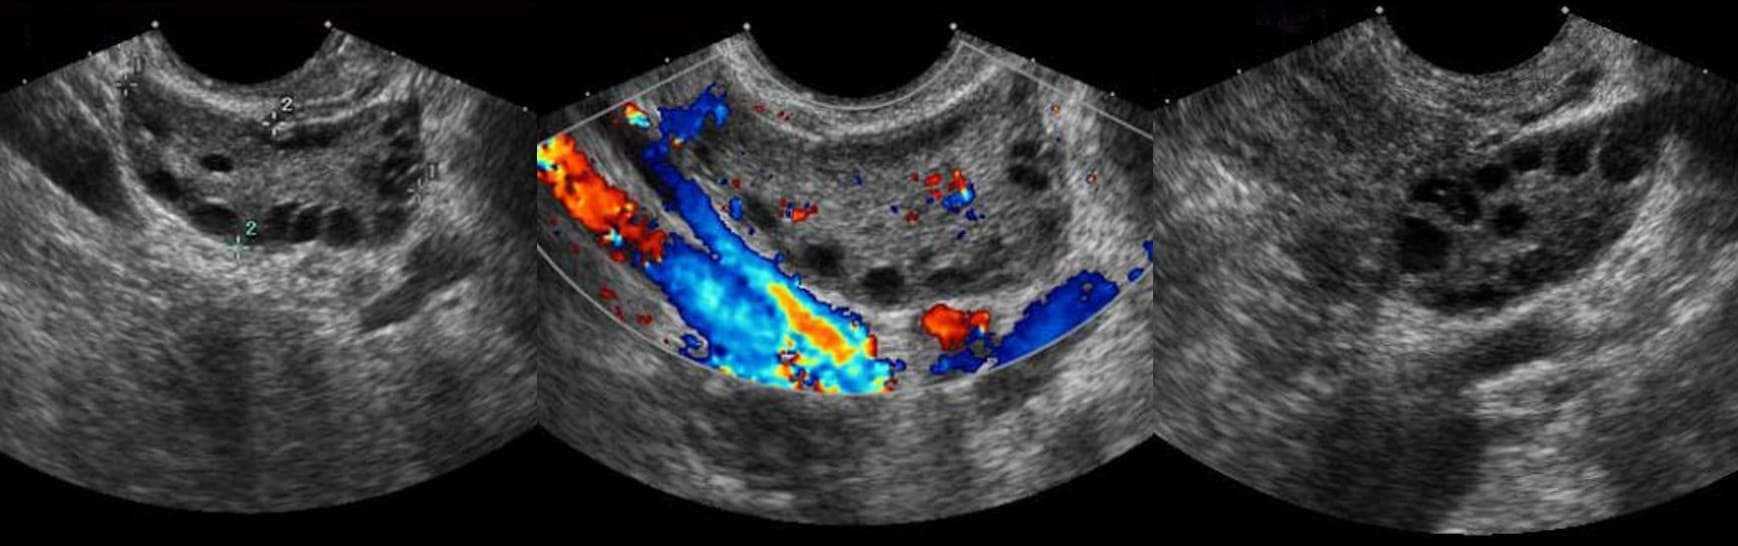

УЗИ органов малого таза – это исследование ультразвуком, позволяющее визуально оценить состояние органов. Для клинической картины поликистоза характерно увеличение желез в 2-3 раза и образование на них кистообразных гроздей, напоминающих виноград.

Ультразвуковое исследование. На УЗИ определяется увеличение яичников, появление кистозных включений – мелких фолликулов размерами до 1 см числом не менее 10.

Допплерометрия. При оценке кровотока отмечается выраженная сосудистая сеть в строме органа.